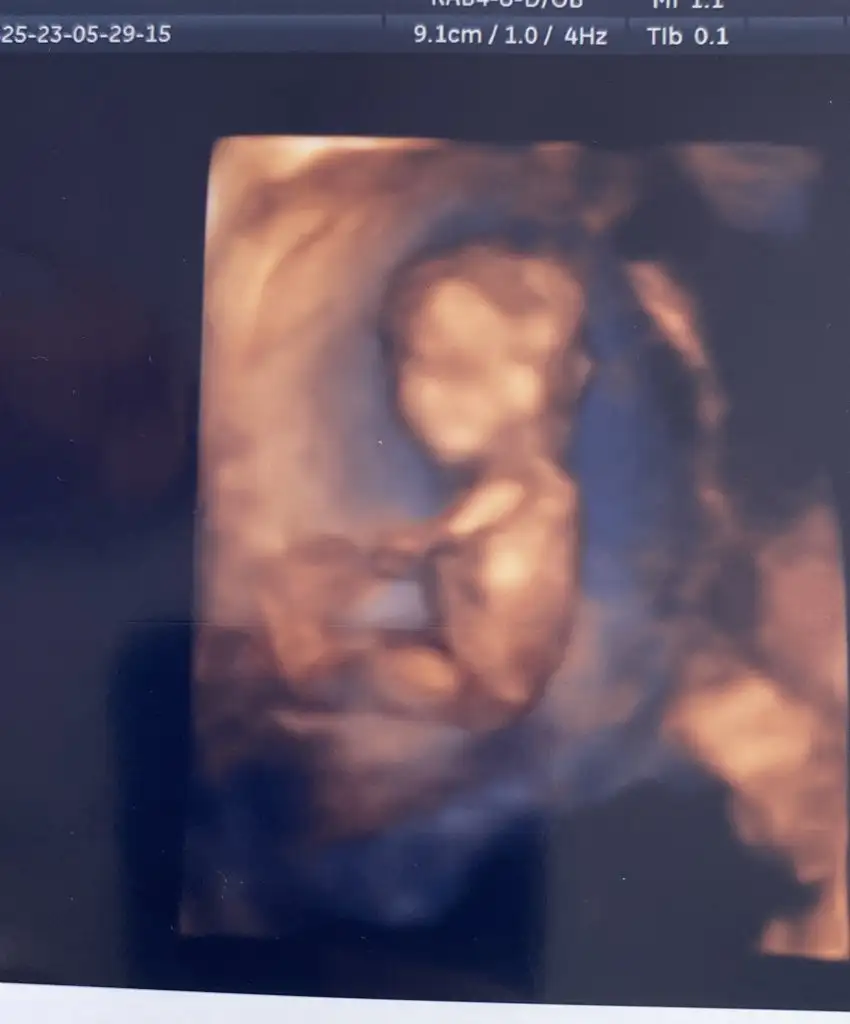

MaşallahSelam teyzeler cinsiyetimi göstermedimuzattım bacaklarımı kollarımı 12+3

Bacak arasında kordon vardı canım bende çok önemli değil cinsiyet dedim pek üstelemedim bu aylarda yanılma payı oluyor çünkü en sağlıklısı 16.hafta çok merak edersen 2 hafta sonra gel dedi ama 16.haftada gitmeye düşünüyorumMaşallahe doktorun bi tahmini var mı peki yapısından kaynaklı falan